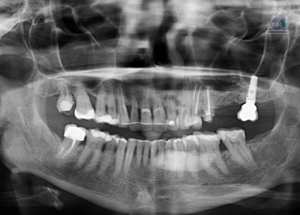

PACIENTE FEMENINO de 81 años acude al Instituto de Diagnóstico Maxilofacial PARA UNA TOMOGRAFÍA para colocación de implantes. A la evaluación de la radiografía panorámica

Paciente femenino de 58 años acude al Instituto de Diagnostico Maxilofacial para realizarse una tomografía para la colocación de implante dentales. A la evaluación de